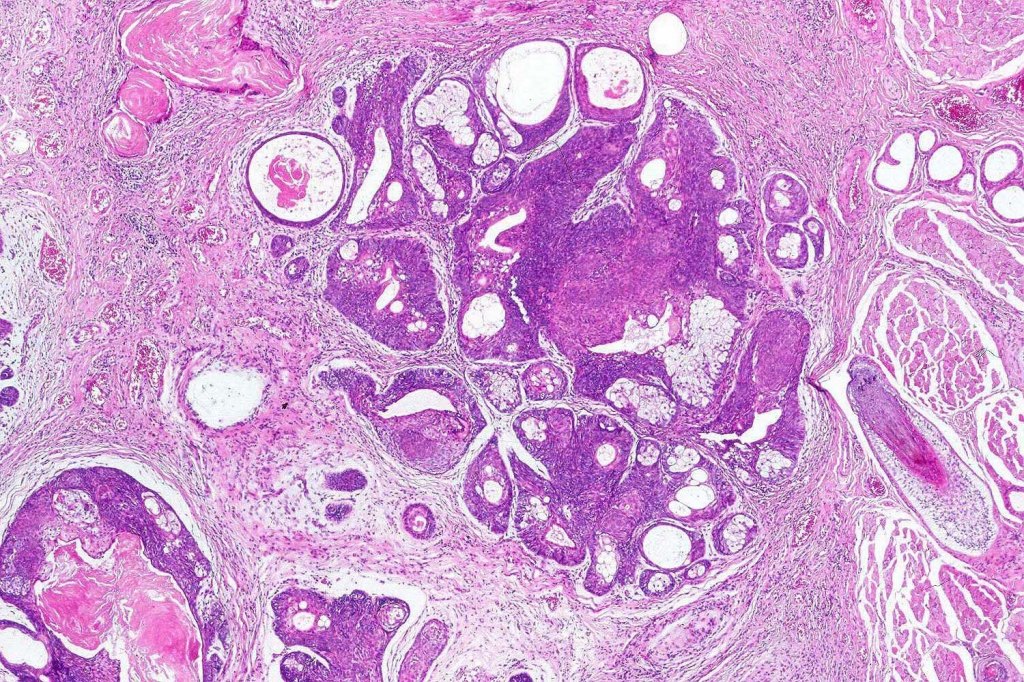

Histological features

•Variable continuity with epidermis

•Multinodular with surrounding collagenous stroma

•Random distribution of basaloid cells & sebocytes (<50% sebocytes)

•Duct formation, often with holocrine secretion generally present

•Mitoses sparse to conspicuous

•Absent peripheral palisading & retraction artifact

•Cystic variant

•Subtypes include rippled pattern, carcinoid-like & reticulated